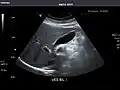

Left kidney -

Kidneys: Right and left kidneys measure 11.5 cm and 12 cm in length respectively. No hydronephrosis. Small left lower pole kidney cyst.